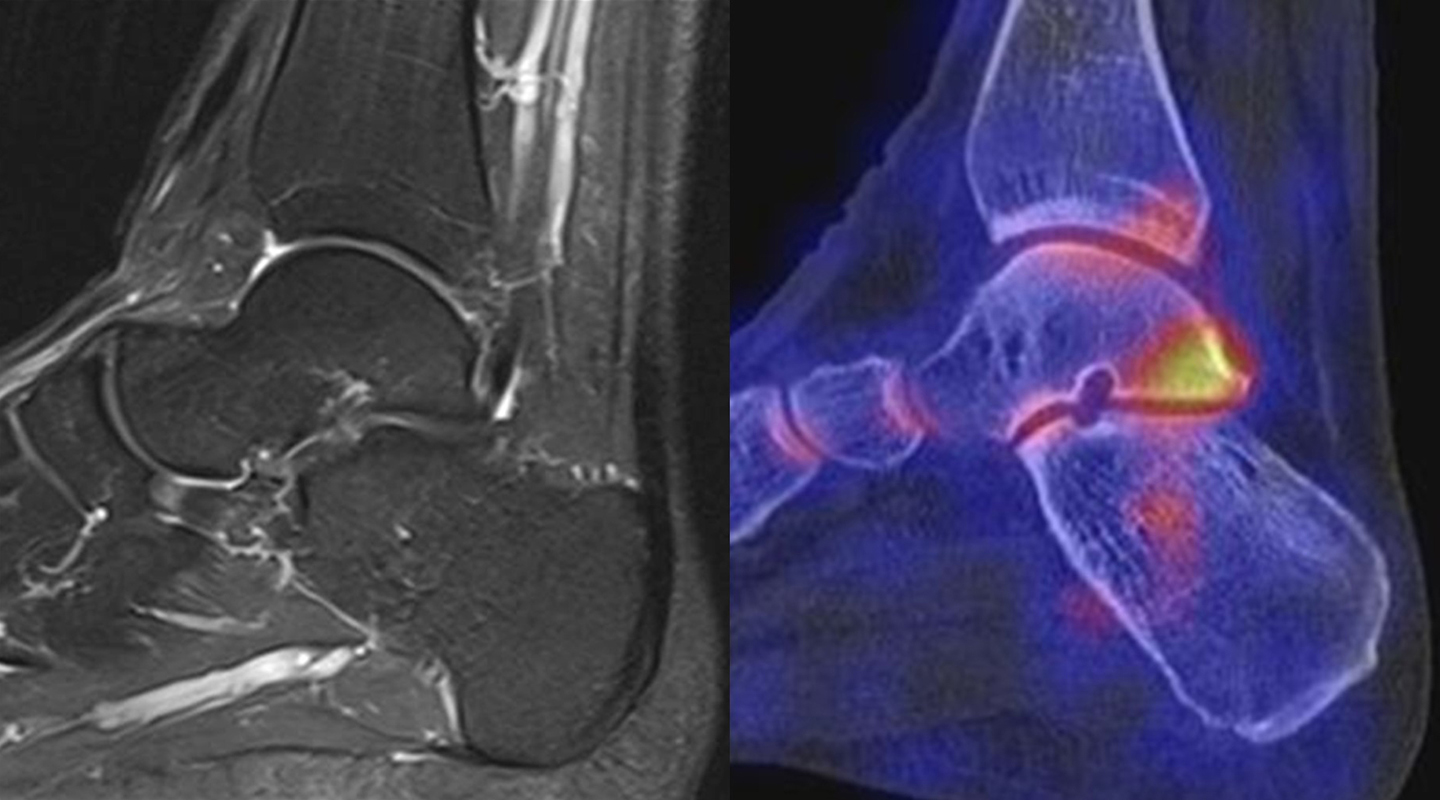

Abbildung 2.1.

Bildbeispiele symptomatische OCL

Zum Lesen der Bildbeschreibung und zur Vollansicht bitte das Bild anklicken. Bild: H. C. Rischke

Abbildung 2.2.

Bilder eines Patienten mit Z. n. mehrfachen Sprunggelenksdistorsionen in der Vergangenheit, besonders heftige Distorsion des linken Sprunggelenkes 5 Wochen vor der Untersuchung. Die SPECT/CT zeigt eine instabile osteochondrale Läsion mit deutlicher Aktivierung.

Abbildung 2.3.

Klärung bei Schmerzen im rechten OSG bei OCL an der medialen Talusschulter. Z. n. OSG-Distorsion vor 2 Jahren und Z. n. OSG-Fraktur / Syndesomosenruptur. Ausgedehnte OCL, hier jedoch kein erhöhter Knochenmetabolismus; lediglich Nachweis einer Stressreaktion im Bereich der Synchondrose eines Os trigonum als Schmerzursache.